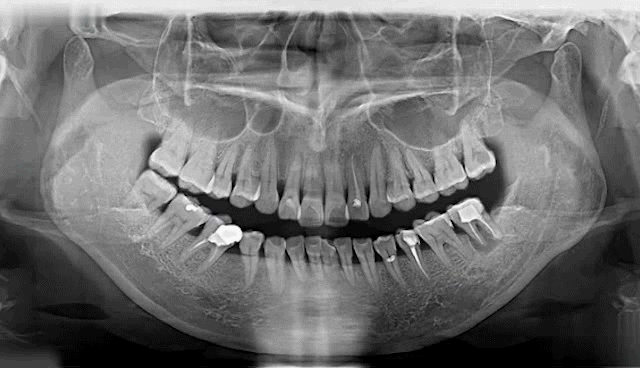

(多颗种植示例)

种植牙是医学界公认的理想修复方式,被誉为“人类的第三副牙”。相比活动假牙不舒服、难清洗、容易引起口腔黏膜病变,种植牙更稳固耐用,舒适美观,咀嚼功能好,一次种植,终生受用。种植牙不仅是中老年人的专利,年轻人因意外、牙病等造成牙齿缺失,也能够通过种植牙进行修复治疗,重获美丽笑容。

牙齿缺失会引起邻牙松动、对牙伸长、引发牙周病,最终牙齿脱落等一系列问题,还会因咬合紊乱致使面容苍老、咀嚼功能变差引发肠胃疾病,甚至影响身体健康。